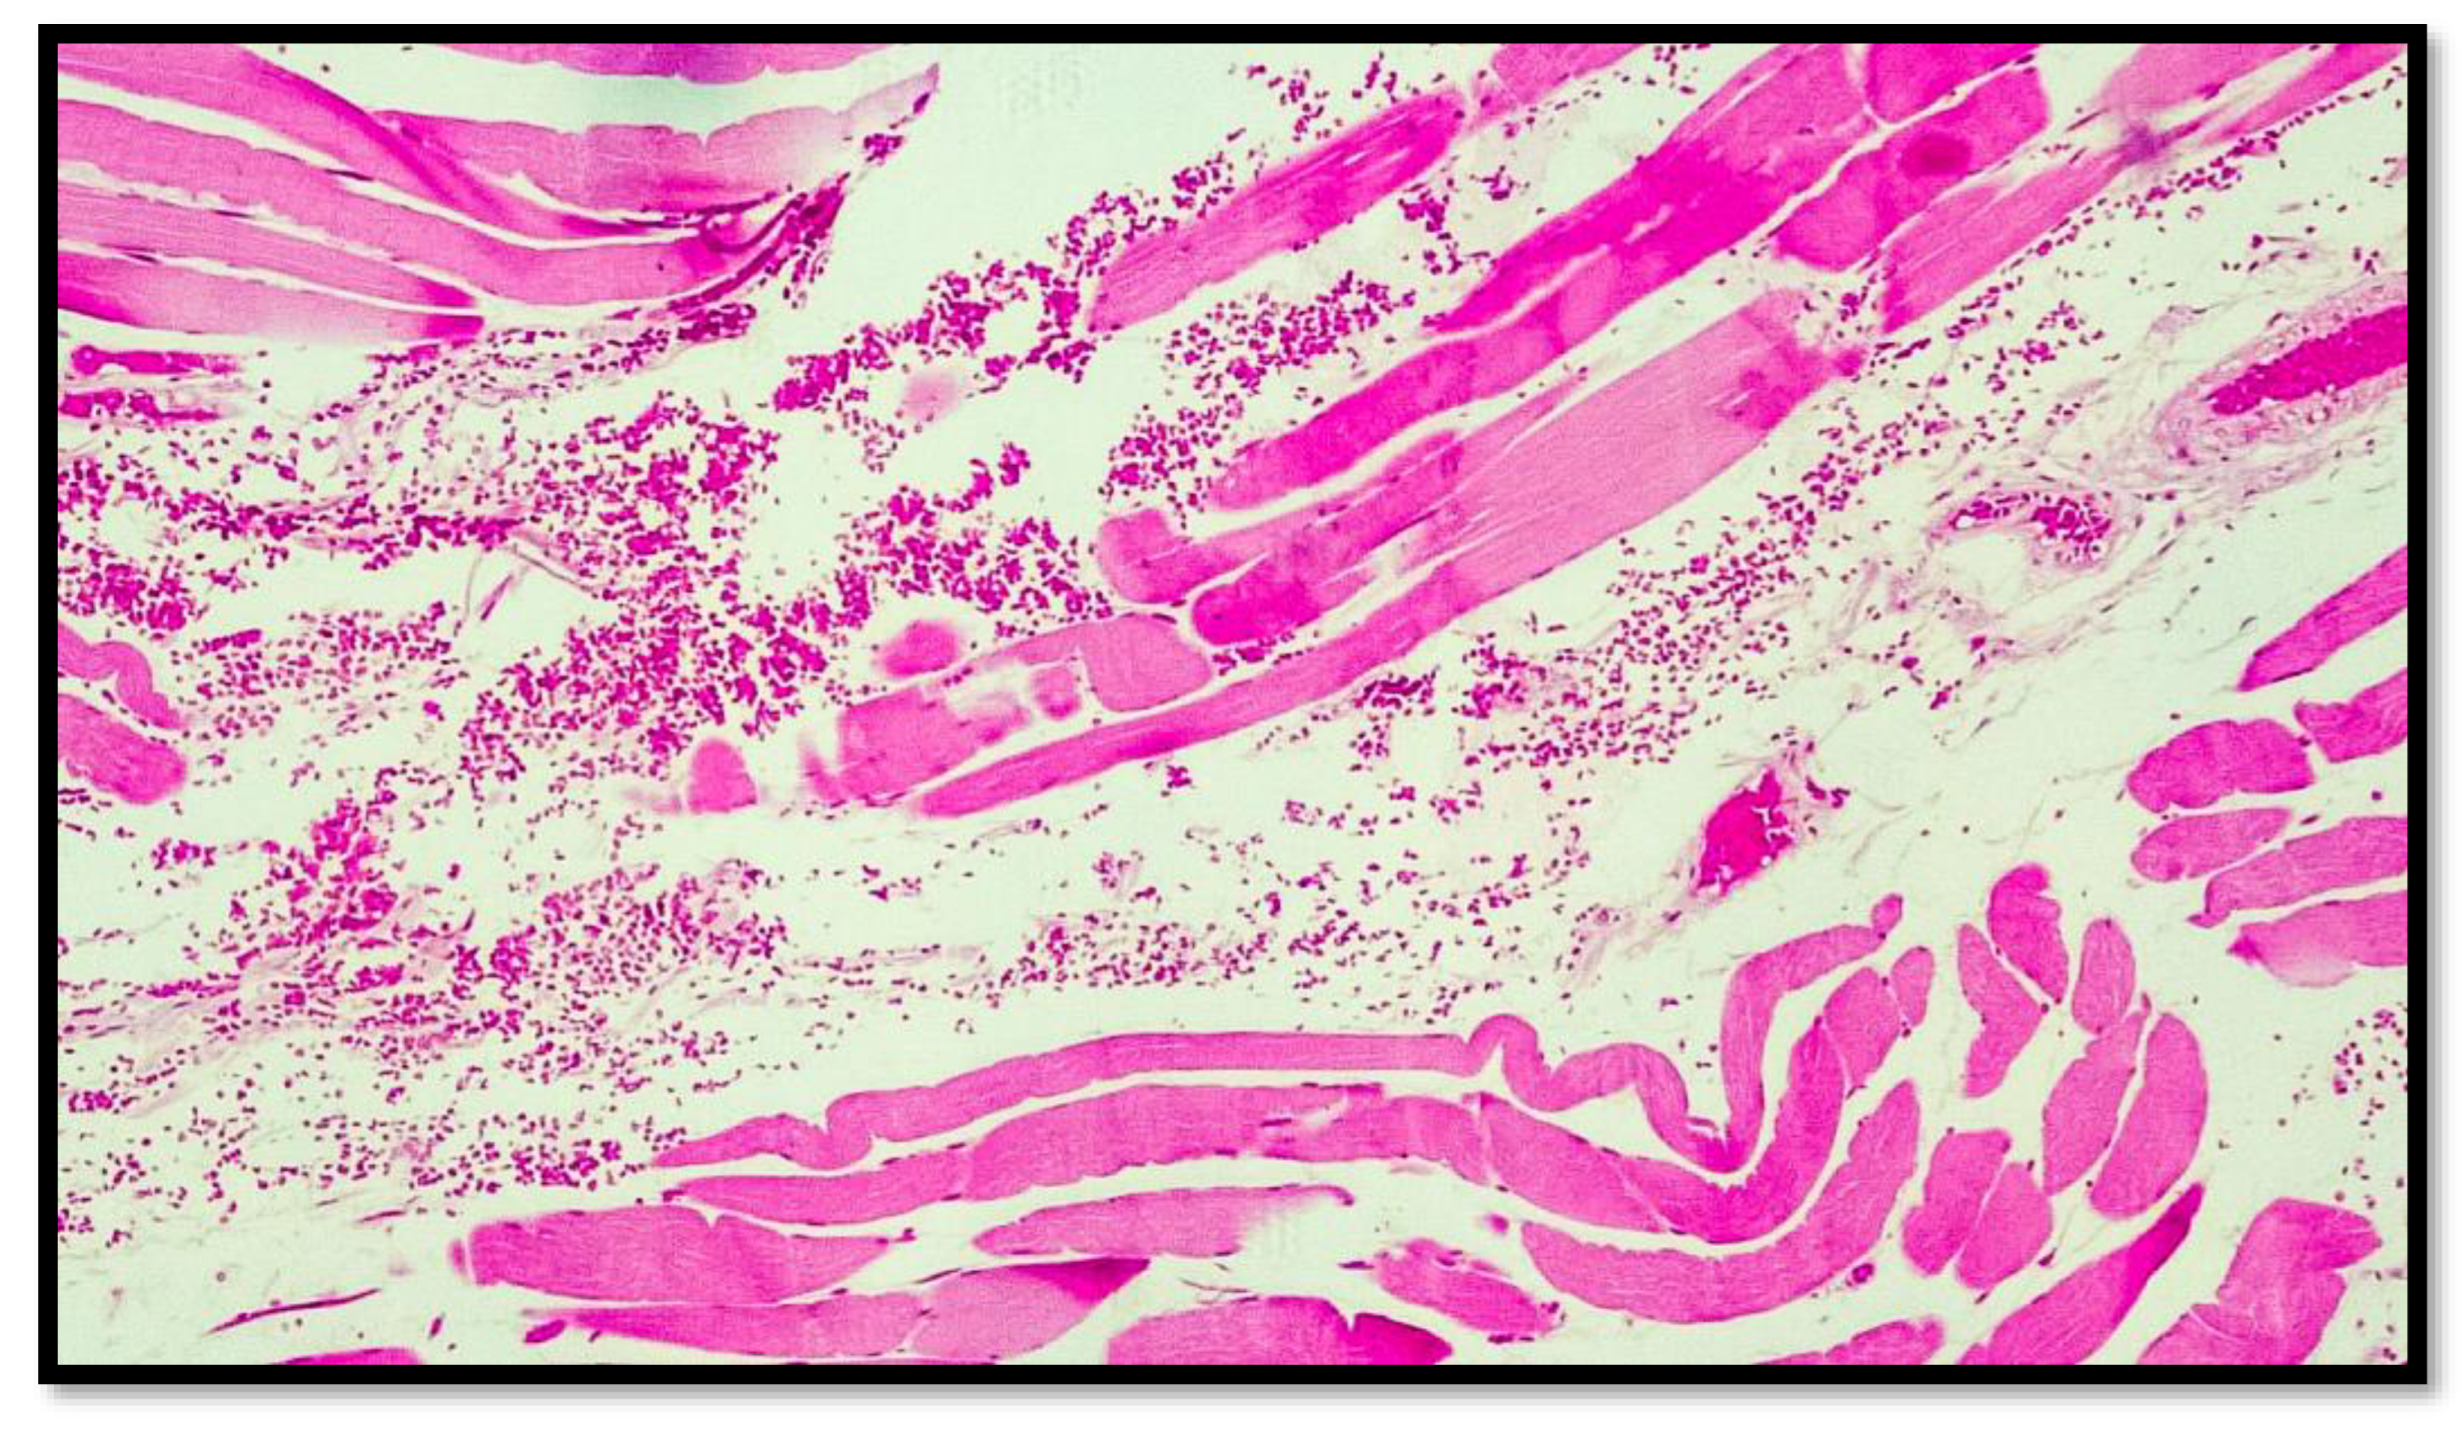

- (1)

- Excoriations and septal hemorrhages at the level of the sulcus, with hemorrhagic extravasations into the dermis, subcutaneous, and interstitial tissues of the neck;

- (2)

- Lesions of the carotid intima (Amussat’s sign);

- (3)

- Minute hemorrhages of the adventitia of the common carotid artery (Friedberg’s sign);

- (4)

- Fragmentation of the myelinated fibers of the vagus nerve (the sign of Dotto);

- (5)

- Hemorrhages in the cervical lymph nodes (Jankovich and Incze’s sign);

- (6)

- Retropharyngeal and paravertebral ecchymosis produced by compression of the base of the tongue against the pharynx (Brouardel’s sign);

- (7)

- The presence of subconjunctival and endocardial hemorrhagic petechiae, indicative of overinsufflation;

- (8)

- Hemorrhages below the anterior longitudinal ligament in the dorso-lumbar segment;

- (9)

- Tumidity of the penis and spermatorrhea [7].